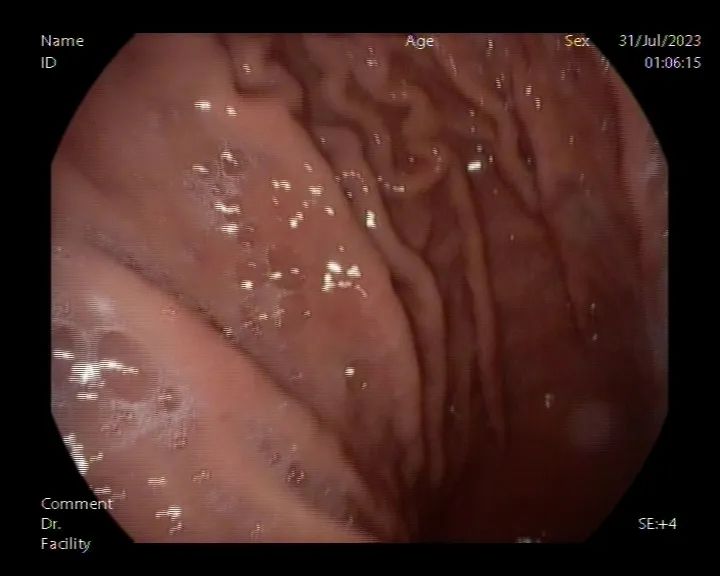

术后,孙先生意外的是,医生开出的治疗方法竟是喝可乐。“喝可乐可以帮助胃里的石头溶解,从而通过排便排出体外。”医生的一番话解开了孙先生的疑惑。于是,在使用抑酸剂及胃黏膜保护剂的同时,孙先生每天喝1000毫升的可乐,持续四天。让人惊喜的是,四天后再次复查胃镜时,胃内的小结石已经溶解消失,他心里的石头也落了地。

术后复查